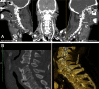

Traumatic brain injury (TBI) is the principal cause of invalidity and death in the population under 45 years of age worldwide. This mini-review aims to systematize the forensic approach in neuropathological studies, highlighting the proper elements to be noted during external, radiological, autoptical, and histological examinations with particular attention paid to immunohistochemistry and molecular biology. In the light of the results of this mini-review, an accurate forensic approach can be considered mandatory in the examination of suspected TBI with medico-legal importance, in order to gather all the possible evidence to corroborate the diagnosis of a lesion that may have caused, or contributed to, death. From this point of view, only the use of an evidence-based protocol can reach a suitable diagnosis, especially in those cases in which there are other neuropathological conditions (ischemia, neurodegeneration, neuro-inflammation, dementia) that may have played a role in death. This is even more relevant when corpses, in an advanced state of decomposition, are studied, where the radiological, macroscopic and histological analyses fail to give meaningful answers. In these cases, immune-histochemical and molecular biology diagnostics are of fundamental importance and a forensic neuropathologist has to know them. Particularly, MiRNAs are promising biomarkers for TBI both for brain damage identification and for medico-legal aspects, even if further investigations are required to validate the first experimental studies. In the same way, the genetic substrate should be examined during any forensic examination, considering its importance in the outcome of TBI.